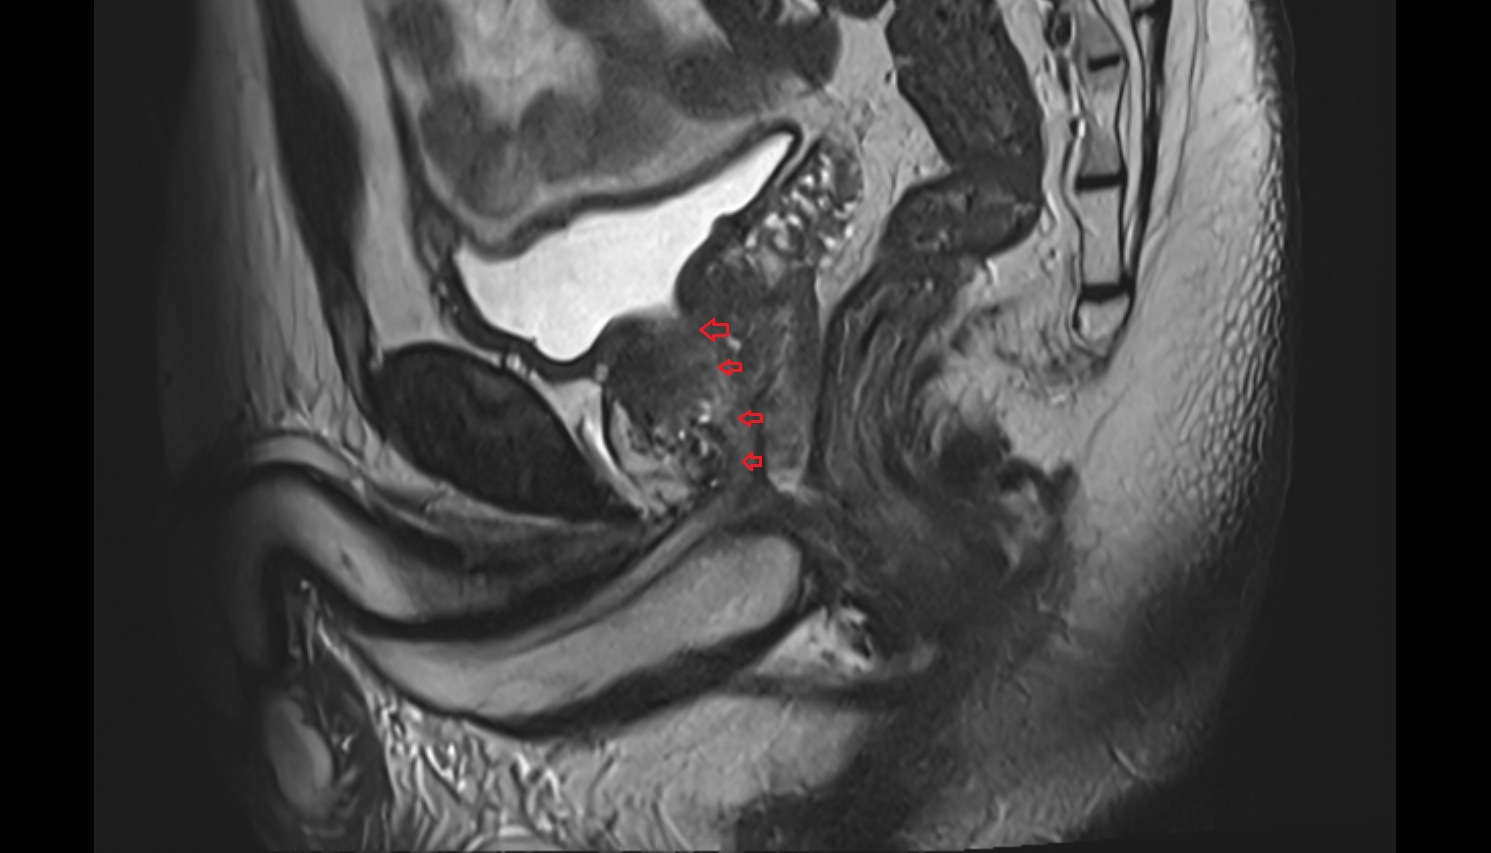

- Uterus

- Body of uterus

- Fundus of uterus

- Cervix of uterus

- Isthmus of uterus

- Vagina

- Fornix of the vagina

- Endometrium of uterus

- Myometrium of uterus

- Perimetrium of uterus

- Junctional zone of uterus